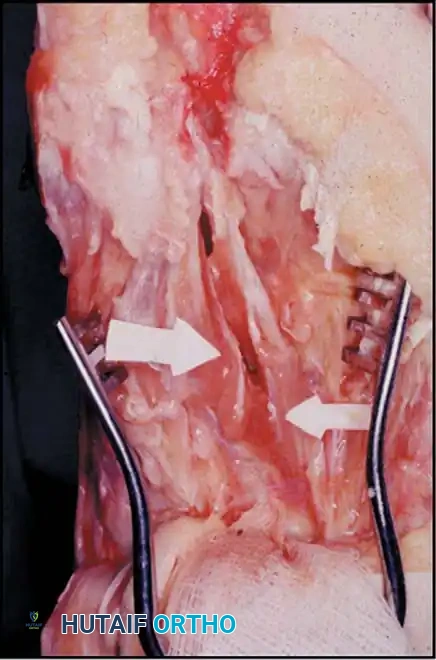

Fig. 78-32 Firm fi brous band connects fi bular sesamoid to base of proximal phalanx. Traction on band pulled hallux into valgus. Removing fi bular sesamoid and holding hallux straight for 4 weeks improved results.

Presumably, the laterally displaced fi bular sesamoid, when pulled proximally by the lateral head of the relaxed fl exor hallucis brevis, pulls the fl exor hallucis longus laterally through the sesamoid apparatus, which encases it and contributes to recurrent hallux valgus. In addition, while reoperating after a failed Keller procedure, we observed a strong, linear, fi brous attachment of the fi bular sesamoid to the proximal phalangeal remnant (Fig. 78-32), which pulled the hallux into valgus when tension was applied to it. For these reasons, when the deformity is severe, the hallux and fi rst metatarsal maintain better alignment if excision of the fi bular sesamoid and lateral displacement of the metatarsal are added to the procedure. joint, lateral capsulotomy at the metatarsophalangeal joint, and lengthening of the extensor hallucis longus tendon. Hohmann recommended lateral displacement and plantar tilting of the distal fragment, following osteotomy at the metatarsal neck to correct hallux valgus. In 1945, a report by Mitchell et al. of 100 osteotomies gave the procedure his name. Since then, several authors have presented large retrospective reviews of the Mitchell operation to correct hallux valgus in adults and adolescents, with satisfactory results ranging from 74% to 94%. Gibson and Piggott described a peg-in-hole distal metatarsal osteotomy that differed from the Mitchell procedure in its use of a lateral plantar spike on the proximal fragment in place of the lateral spike on the distal fragment (as recommended by Mitchell). The nonunion rate has been negligible in all series of the Mitchell procedure, and recurrence of the deformity has been infrequent. The most troublesome complication has been metatarsalgia, attributable to dorsifl exion malunion of the distal fragment, excessive shortening of the metatarsal, or both (Fig. 78-33). In a long-term (average 21 years) follow-up study of 105 Mitchell procedures, Fokter, Podobnik, and Vengust found that the most common complication was recurrent hallux valgus with medial eminence pain. Their good-to-excellent results deteriorated from 97% at follow-up ranging from 2 to 11 years to 64% at follow-up ranging from 15 to 24 years, primarily because of recurrence of deformity with medial eminence pain. The use of a Kirschner wire for fi xation (instead of sutures) prevented malunion; all osteotomies healed in 6 weeks with only secondary displacement. Likewise, with the pegin-hole procedure, metatarsalgia has been the most common complication. Relief of pain, narrowing of the forefoot, and correction of the deformity have been achieved in most patients, however. A closing wedge osteotomy at the subcapital level of the fi rst metatarsal to correct valgus of the hallux also has its proponents. Although opponents emphasize that metatarsus primus varus is worsened, and recurrence of the valgus deformity of the great toe is likely, published series have not confi rmed this. Of 32 osteotomies reported by Peabody and 76 reported by Funk and Wells, no nonunions or signifi cant recurrences of the deformity were recorded. A popular osteotomy of the distal metatarsal is the chevron intracapsular osteotomy, which was described by Corless in 1976 as a modifi cation of the Mitchell procedure to correct the bunion associated with mild-to-moderate metatarsus primus varus. The procedure consists of two parts: (1) correction of metatarsus primus varus by a V shaped osteotomy in the sagittal plane through the metatarsal head and neck, followed by lateral shifting of the metatarsal head and trimming of the proximal fragment without internal fi xation (because of the inherent stability of the osteotomy) and (2) correction of the hallux valgus by suturing a previously raised fl ap of joint capsule into the abductor hallucis tendon. Several series of this osteotomy with adequate clinical follow-up have been published. Austin and Leventen reported, in 100 osteotomies randomly selected for analysis from a group of 1200, that no nonunions, osteonecrosis, or infections occurred. Hattrup and Johnson reported, in 225 feet (157 patients), that pain, shoe fi t, and cosmesis were improved in all but a few patients. Because their best results were in younger patients, the authors indicated that